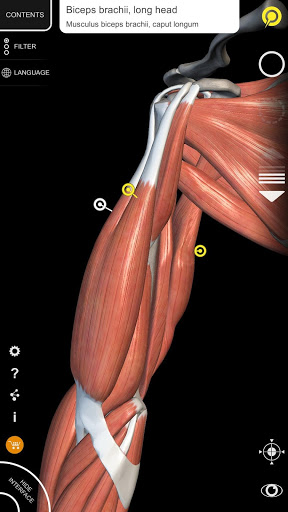

Завдяки простому та інтуїтивно зрозумілому інтерфейсу можна спостерігати кожну анатомічну структуру під будь-яким кутом.

• Візуалізація м’язів через рівні шарів від поверхневих донизу до найглибших

• Вибравши модель або шпильку, з’явиться відповідний анатомічний термін

• Опис м’язів: походження, приєднання, іннервація та дія